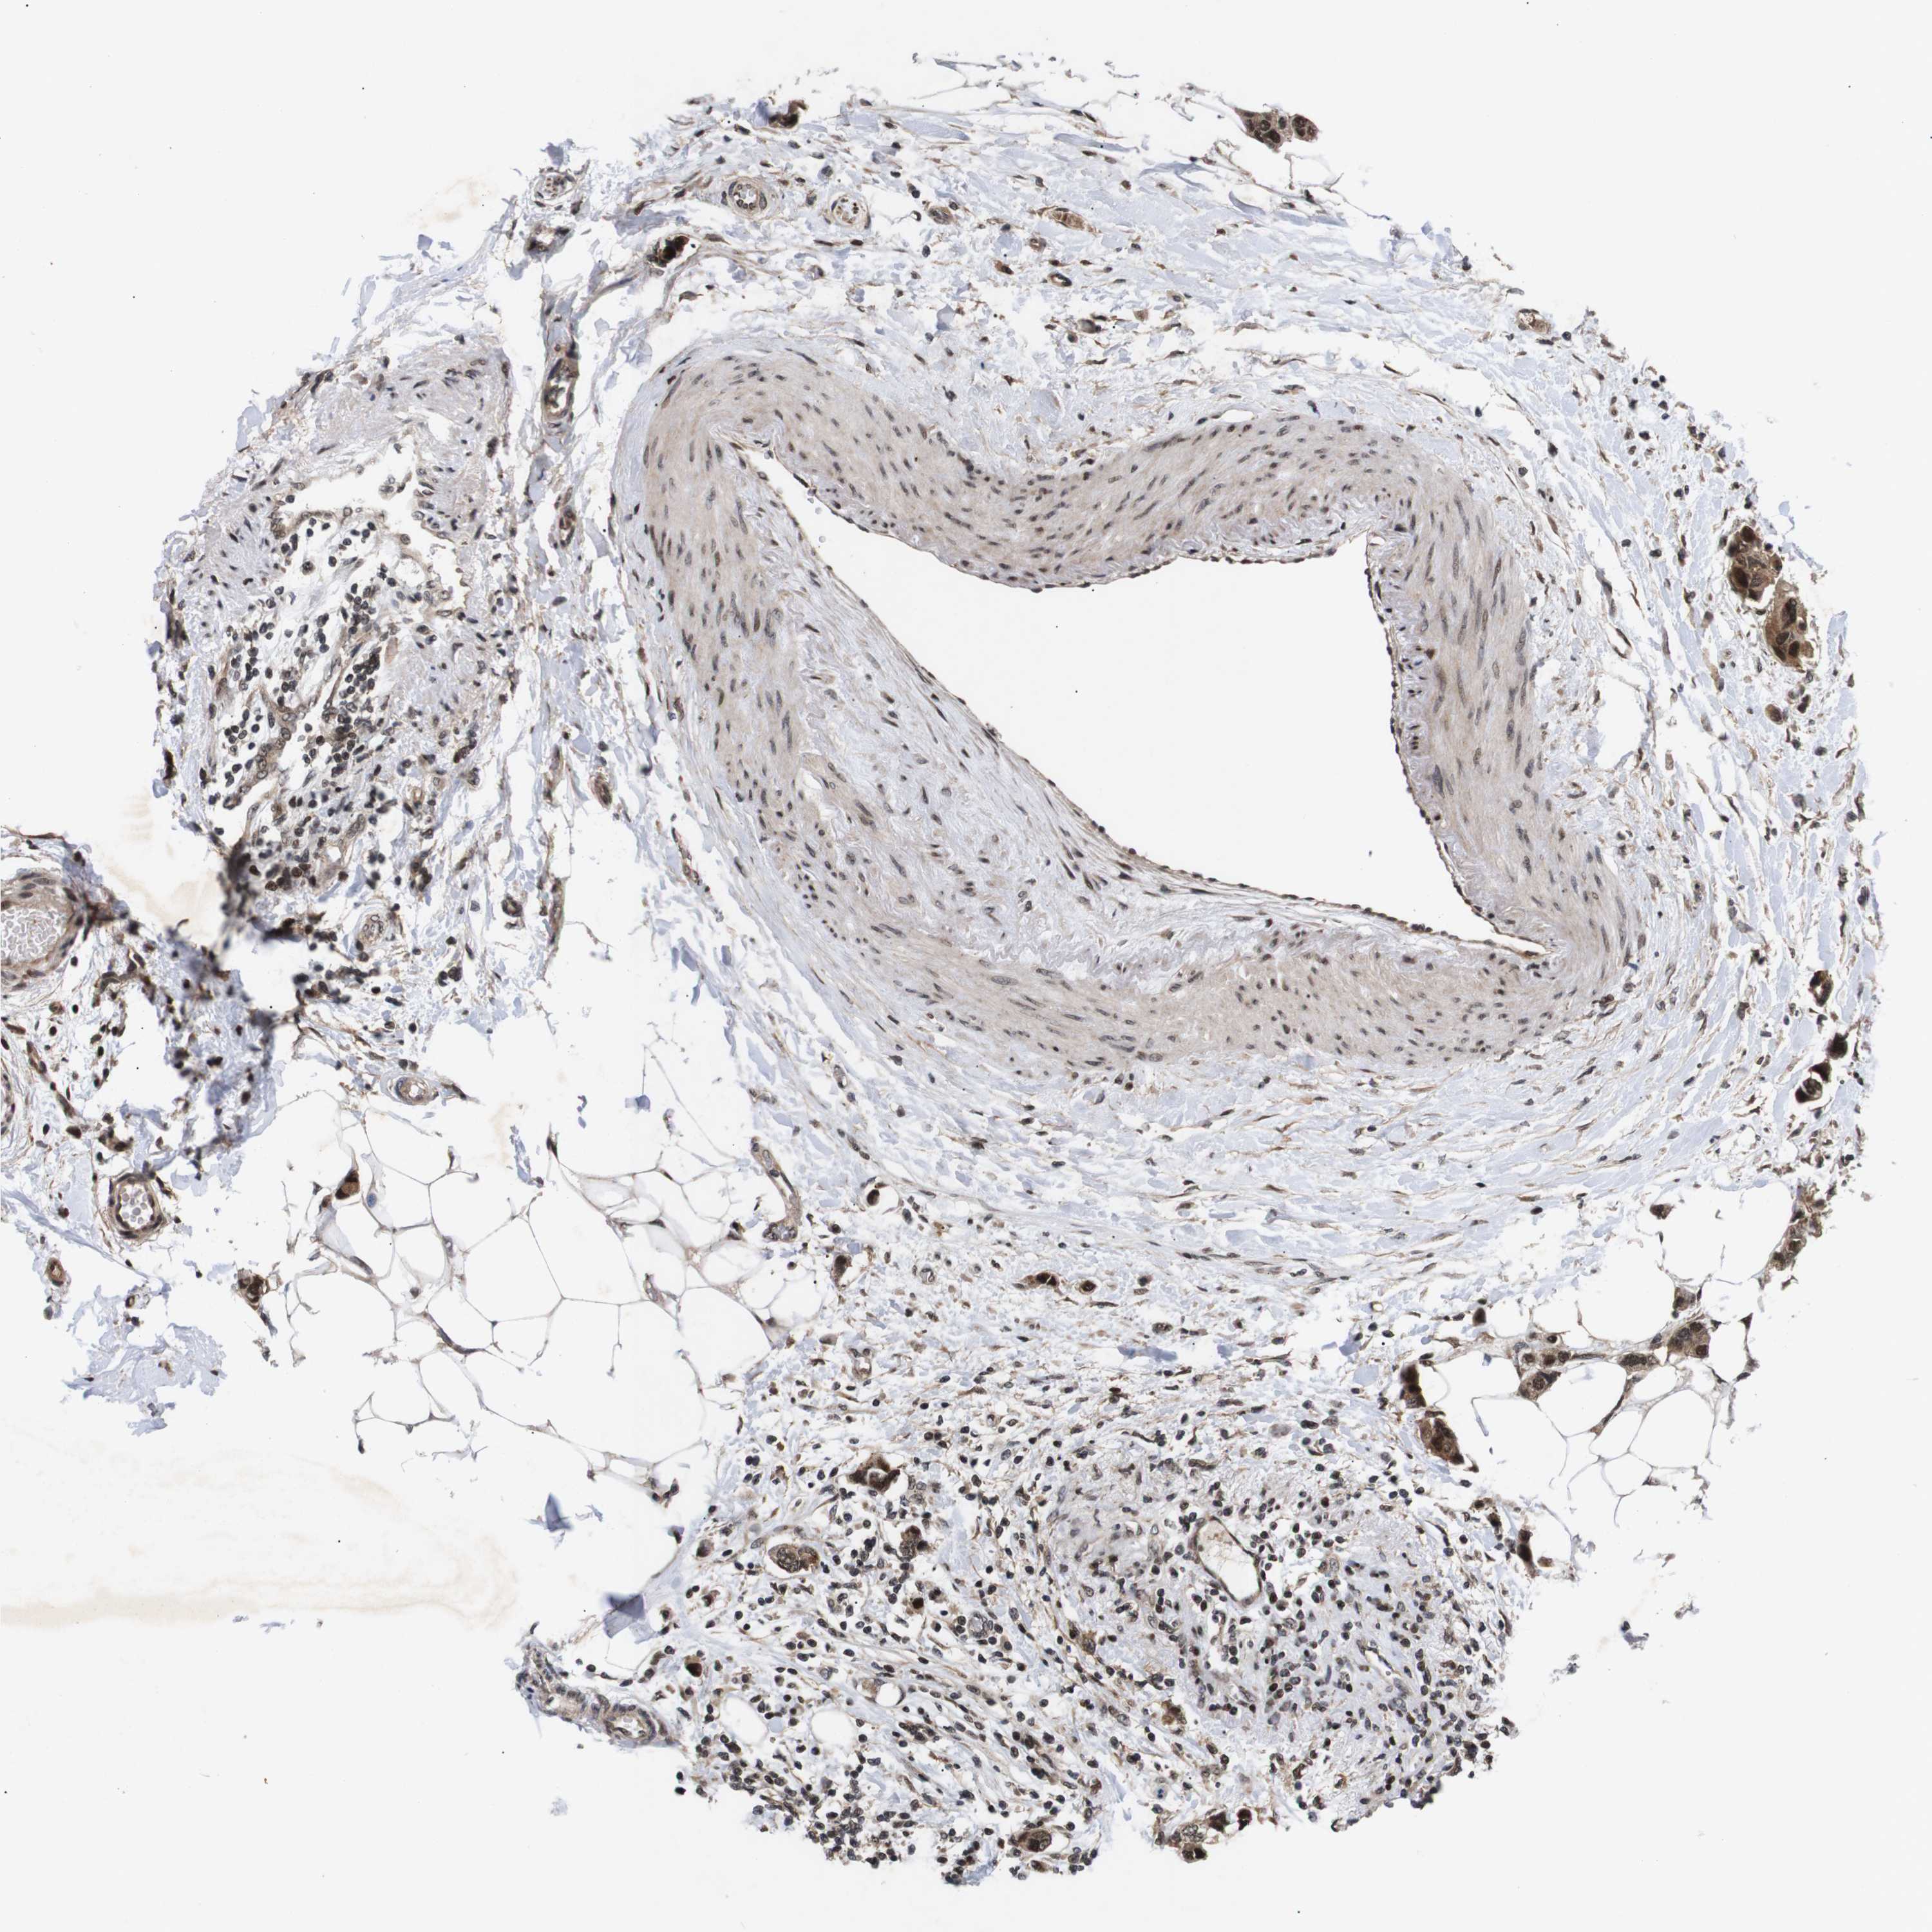

BRCA TCGA BRCA VALIDATION PROTEIN EXPRESSION

ANTIBODIES

AND

VALIDATION